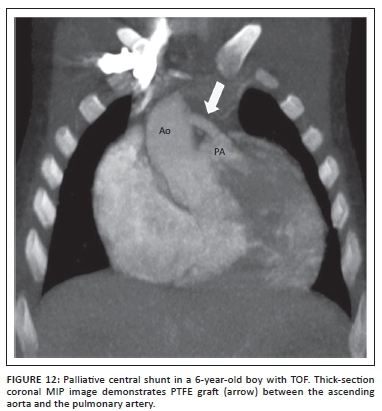

The modified Blalock-Taussig (MBT) shunt (Figure 11) directs blood from the subclavian artery opposite the aortic arch to the pulmonary artery via a PTFE or Goretex conduit graft rather than an end-to-side anastomosis of the ligated and divided native subclavian artery of the CBT shunt. Improved patency rates and ease of subsequent closure, favour the use of these shunts in our institution.

Central shunts using PTFE interposed between the ascending aorta and the main pulmonary artery are also in use. Where echocardiography may be challenging, CTA is once again perfectly suited to establish shunt anatomy and patency (Figure 12).

Pulmonary artery distortion owing to previous palliative shunting in older children lost to follow-up is elegantly displayed at CTA as an alternative to invasive angiography.